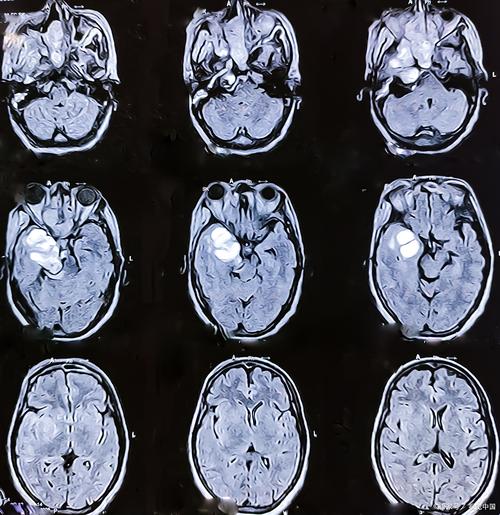

MRI如何显示脑梗和脑软化?

磁共振成像(MRI)是诊断和评估脑梗死的最佳工具,因为它对水分子的变化极其敏感。

B. 慢性期脑梗死的MRI表现(发病数周至数月后)

这个阶段,梗死已经进入终末期,即“脑软化”阶段。

T2加权像 (T2WI) 和 FLAIR 序列

- 表现:高信号(亮白)。

- 原理:囊腔内充满液体(脑脊液),在富含水分的T2序列和FLAIR序列上均呈明显高信号,FLAIR序列能更好地显示皮层和脑室旁的病灶,因为它会抑制脑脊液的信号,使得靠近脑室的病灶更突出。

-

DWI / ADC 序列

- 表现:DWI呈等信号或低信号,ADC呈等信号或高信号。

- 原理:急性期的细胞毒性水肿已经消失,囊腔内的水分子是自由运动的,所以其弥散不受限制,信号恢复正常(与周围正常脑组织相似),这是区分急性期和慢性期最关键的影像学特征。